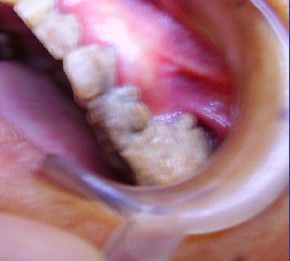

好大的牙结石

今天下午,一患者满怀一副痛苦的表情走进了我们科室,且还有陪同的亲戚,听其亲戚表述,说被我检查的病人怀疑牙龈上长了个瘤,问我是不是癌症,于是乎,我怀着一种很细心的态度去检查她口腔,经过仔细检查,原来是很大的一块牙结石,,我便随手用相机拍下来,以供同行斟酌.